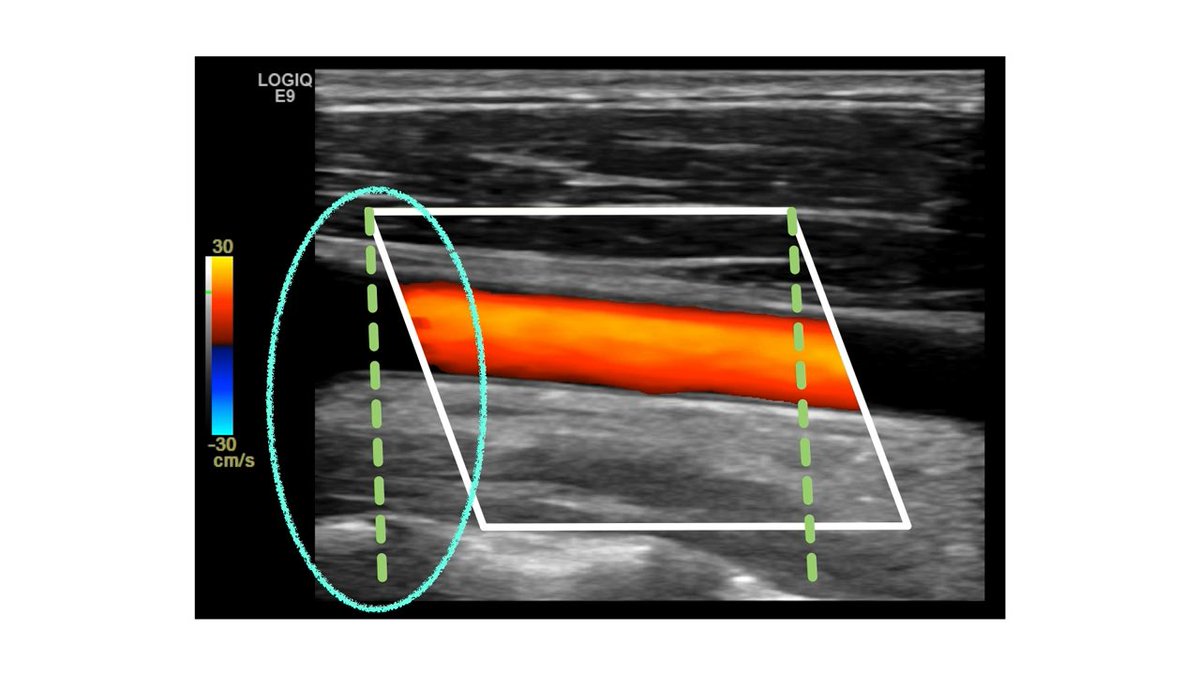

3- color box :

في ” الـ linear probe ” اذا فتحنا الـ box نشوف الزاويتين الي فوق ونرسم خط تخيلي لتحت ( الخط الي برا المربع هو الي يكون بجهة البروب ) ومنه راح نستنتج مكان البروب ( يمين او يسار )

طبق المعايير الي فوق على هالصورتين وبتعرف هل الاتجاه صحيح او لا